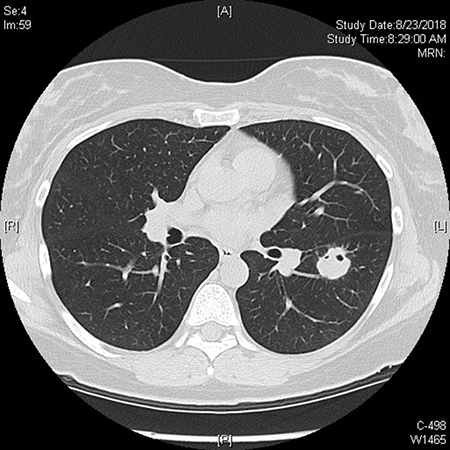

Clinical History: A 2.3 cm left lower lobe nodule was detected in a 45-year-old woman who underwent a screening chest x-ray due to a history of smoking. Subsequent chest computed tomography (CT) showed a nodule with irregular margins and small peripheral foci of air at the inferior margin, possibly reflecting eccentric cavitation or underlying air bronchograms. Foci concerning for mucoid impaction were noted. A CT-guided fine needle aspiration and biopsy were subsequently performed.